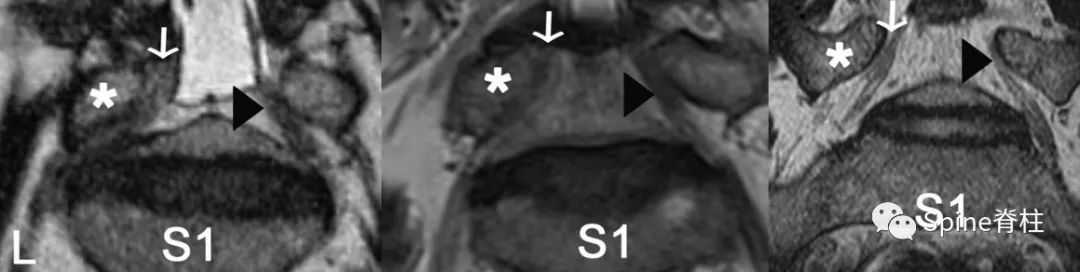

图示:斜冠状位磁共振成像,以L5脊神经为代表。L5脊神经在L5椎弓根(*)和L5-S1椎间盘之间通过。

- 左侧图: 在腰椎间孔外狭窄组中,左侧L5神经是引起症状的(白色箭头),而右侧无症状(黑色箭头)。

- 中间图: 在L4-5椎管内狭窄组中,左侧L5神经为症状性侧(白色箭头),右侧为无症状性侧(黑色箭头)。

- 右侧图: 在正常人组中,显示的右侧(白箭头)和左侧(黑箭头)L5脊神经。